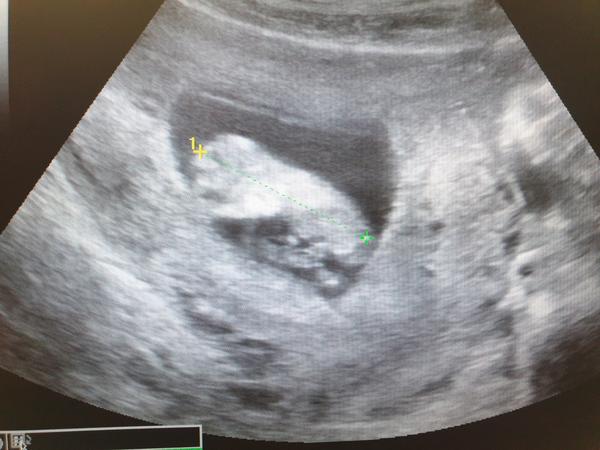

Já byla dnes na kontrole a pro prukazku, mimi 12+3tt a úplně tam nadskakovalo rozeviralo pesticky 😍

Doktorka se snažila podívat na pohlaví, říkala ze chlapečci už jsou hezky poznat, takhle poznala i syna ve 12tt ale teď to neslo tak dobře vidět, podezření nějaký má ale zatím mi to napsat nechtěla, tak uvidíme na screeningu a případně jdu na další kontrolu 30.1 v 17tt což už by mělo jit hezky vidět tak uvidíme ❤️